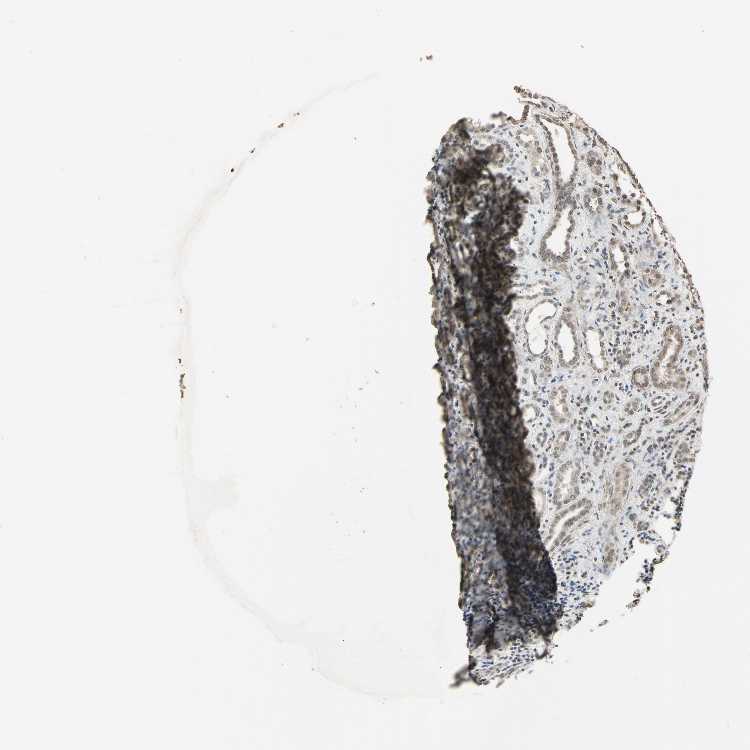

KIDNEY - Antibody stainingi

Antibody staining in the annotated cell types in the current human tissue is reported as not detected, low, medium, or high, based on conventional immunohistochemistry profiling in selected tissues. This score is based on the combination of the staining intensity and fraction of stained cells.

Each image is clickable and will lead to virtual microscopy that enables deeper exploration of all samples and also displays staining intensity scores, fraction scores and subcellular localization as well as patient and tissue information for each sample.

Antibody HPA009656

Cells in glomeruli Medium

Cells in tubules Low